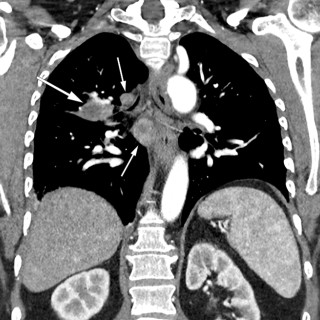

Kronisk transplantat-mot-vert-sykdom er en senkomplikasjon etter allogen stamcelletransplantasjon, og medfører kronisk inflammasjon og fibrose i forskjellige organer på grunn av feil regulering av donors immunceller. Sykdommen kan forekomme i alle organer, men sees hyppigst i hud, øyne, munnhule, gastrointestinaltraktus, genitalia, lunger, muskler, fascier og ledd. Kronisk transplantat-mot-vert-sykdom er assosiert med betydelig sykelighet og dødelighet, og behandling krever tett samarbeid mellom forskjellige deler av spesialisthelsetjenesten. Vi gir i denne artikkelen en klinisk oversikt over...